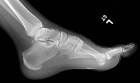

21 year old male with swelling and pain in left foot for six months

Zoom image: Radiological image Radiological image.